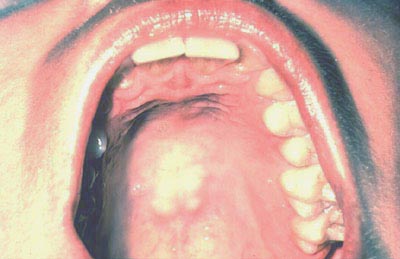

Con la lengua aún elevada, inspeccione el piso de la boca buscando cambios de color, textura, hinchazones u otras anormalidades en la superficie.

Con la boca totalmente abierta y la cabeza del paciente echada hacia atrás, presione suavemente la base de la lengua con un espejo dental. Primero inspeccione el paladar duro y luego el paladar blando.

Examine el paladar blando, úvula, trígono retromolar y los pilares anteriores..